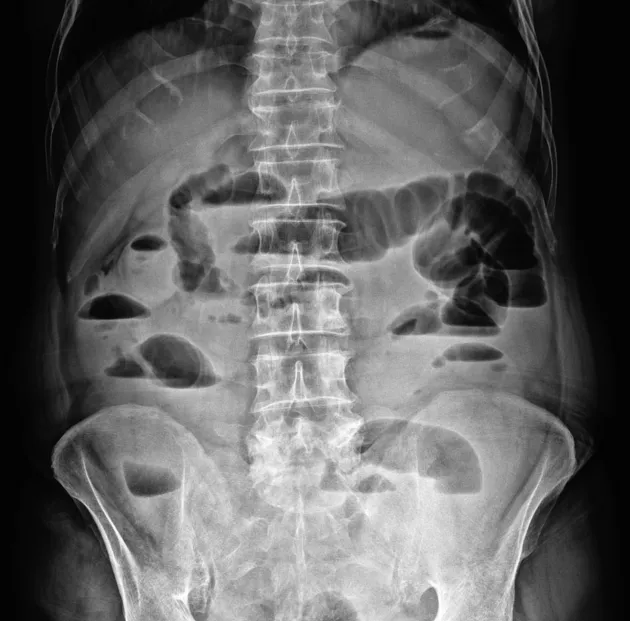

- Abdominal X-ray (supine & erect):

- Dilated bowel loops (small bowel >3 cm, large bowel >6 cm, cecum >9 cm - 📌 3-6-9 rule)

- Multiple air-fluid levels (≥2, >2.5 cm wide)

- String of pearls sign

- Paucity of distal gas

- Imaging: Abdominal X-ray reveals dilated bowel loops proximal to obstruction and multiple air-fluid levels.